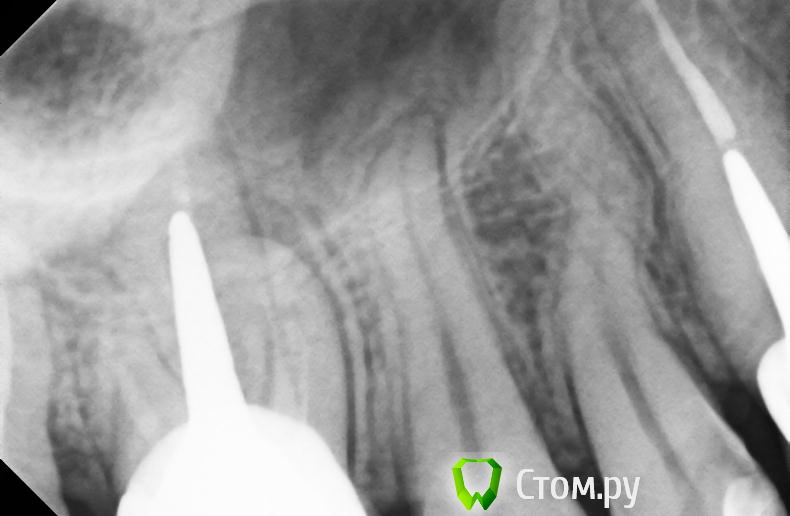

Алексей1983 Опубликовано 7 ноября, 2014 Автор Поделиться Опубликовано 7 ноября, 2014 Дополнительно к панорамному прикрепляю прицельный снимок этого зуба. Ссылка на комментарий

Бобр Опубликовано 7 ноября, 2014 Поделиться Опубликовано 7 ноября, 2014 Для начала сделать рентгенснимок с гуттаперчей в свище, чтобы доказать, что причинный зуб именно шестой. А уже потом думать как вкладку вынимать. корневые каналы в шестом зубе безусловно имеют недоделки Ссылка на комментарий

faity Опубликовано 7 ноября, 2014 Поделиться Опубликовано 7 ноября, 2014 а мне и 5-ый не нравится, плюсую к снимку с гуттой Ссылка на комментарий

Бобр Опубликовано 7 ноября, 2014 Поделиться Опубликовано 7 ноября, 2014 В том то и дело, что и в пятом какие-то намеки у верхушки, да и коронка у него не проснята. А вдруг свищ имеет пародонтальную природу Ссылка на комментарий

victor57 Опубликовано 7 ноября, 2014 Поделиться Опубликовано 7 ноября, 2014 ну а как же гранулема на мезиальном корне 6-го? гутаперча гутаперчей, а я считаю - если терапевты не берутся, и другие не берутся, то что его вытягивать? Ссылка на комментарий

Гарриевич Опубликовано 8 ноября, 2014 Поделиться Опубликовано 8 ноября, 2014 Я бы опили вкладку до небеого штифта, перелечил бы щечный(ые) и в последующем восстановил бы зуб, а небный штифт, использовал как обычный штифт Ссылка на комментарий

Алексей1983 Опубликовано 8 ноября, 2014 Автор Поделиться Опубликовано 8 ноября, 2014 Я бы опили вкладку до небеого штифта, перелечил бы щечный(ые) и в последующем восстановил бы зуб, а небный штифт, использовал как обычный штифтЧто-то подобное мне говорил вчера врач на очном приеме, который согласился лечить этот зуб. А скажите, при таком методе лечения, как вы описываете, есть ли риск перфорации дна гайморовой пазухи (судя по снимкам) и насколько он велик? Дело в том, что те врачи, которые высказывались за удаление, объясняли свое решение в частности тем, что корни этого зуба находятся очень близко к гайморовой пазухе. Ссылка на комментарий

Гарриевич Опубликовано 9 ноября, 2014 Поделиться Опубликовано 9 ноября, 2014 Что-то подобное мне говорил вчера врач на очном приеме, который согласился лечить этот зуб. А скажите, при таком методе лечения, как вы описываете, есть ли риск перфорации дна гайморовой пазухи (судя по снимкам) и насколько он велик? Дело в том, что те врачи, которые высказывались за удаление, объясняли свое решение в частности тем, что корни этого зуба находятся очень близко к гайморовой пазухе.я по плоскому снимку не могу судить о том в пазухе ли зуб или нет. риска перфорации при эндодонтическом лечении в этом случае не вижу. корни в пазухе само по себе не является злом Ссылка на комментарий